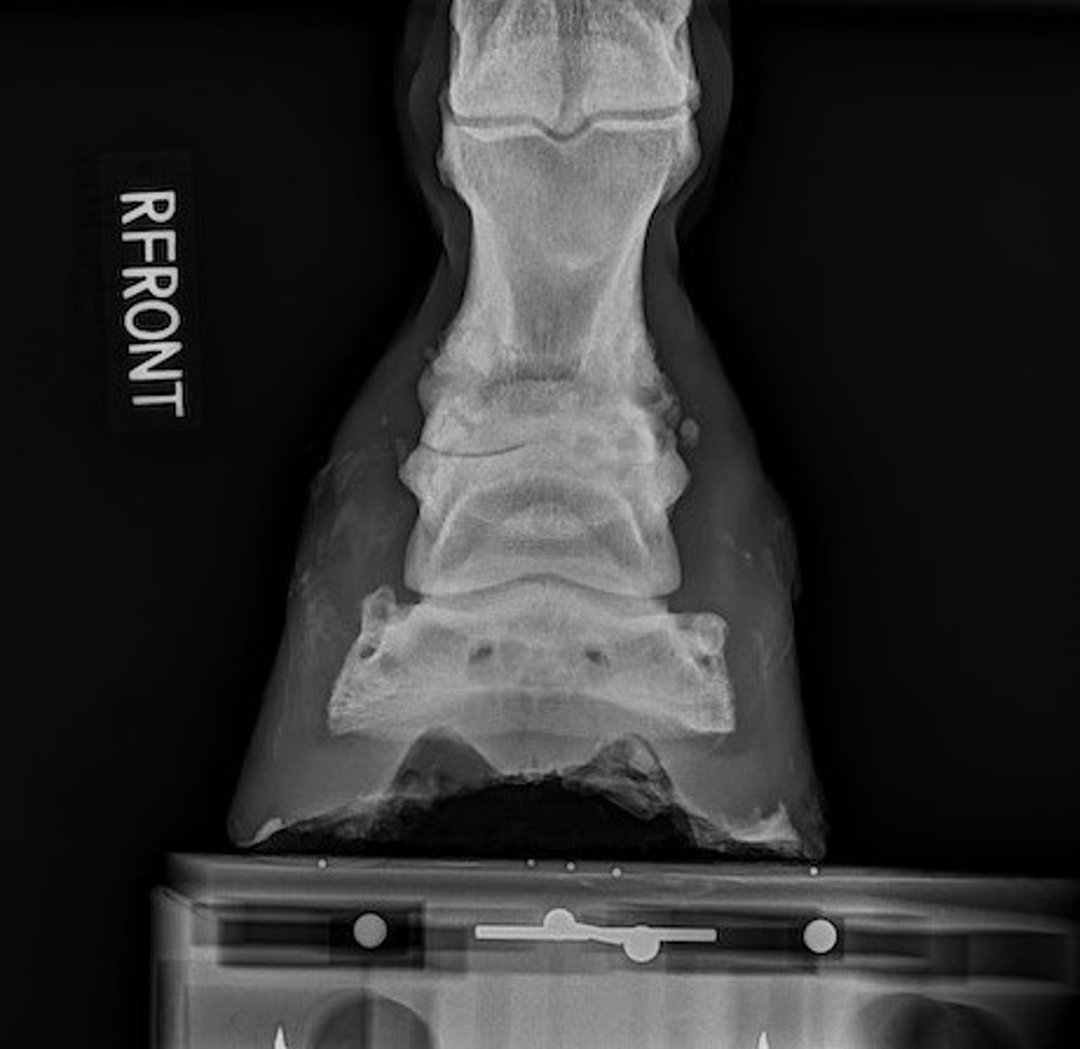

Joint effusion, thickening of the synovial membrane, decreased viscosity of the synovial fluid, and damage to articular cartilage are the hallmarks of OA. Clinical examination might also reveal new bone formation (see pastern OA photograph), loss of normal range of motion, and pain upon flexion of the affected joint. Radiographic changes include narrowing and/or unevenness of the joint space, subchondral bone lysis, subchondral bone sclerosis, osteophyte formation, joint remodeling, and periarticular new bone formation (see pastern OA radiograph).